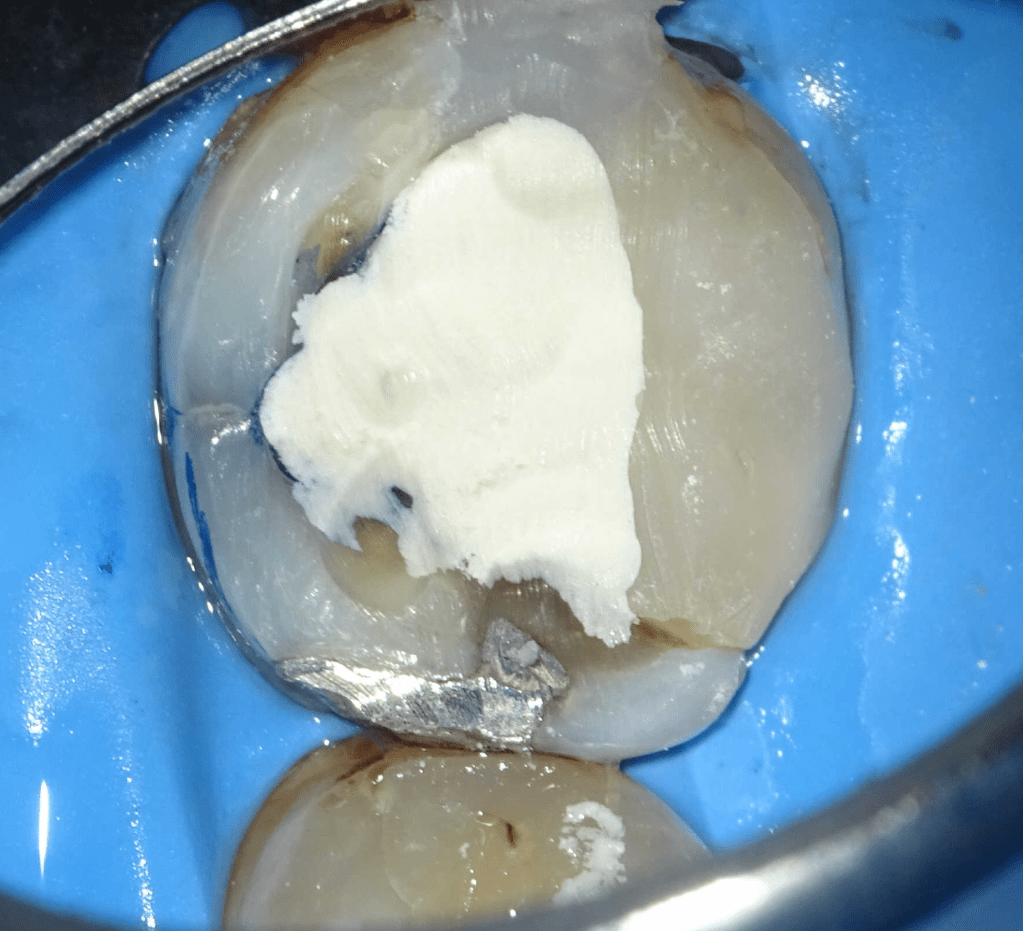

Reconstrucción preendodóntica

Reco preendo + 4 conductos molar superior